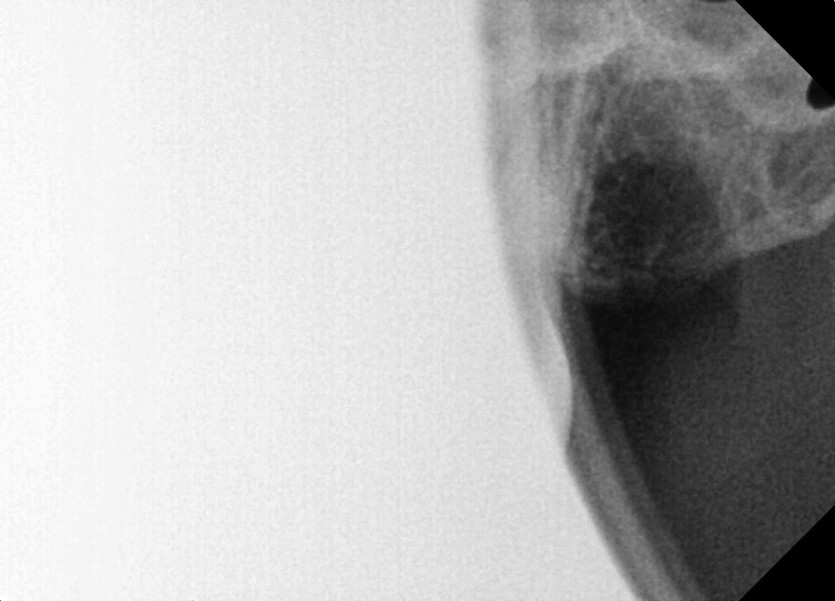

#18,28,38,48 사랑니 발치 (#19과잉치 포함)

구강 외과 전문의가 당일 발치했습니다.